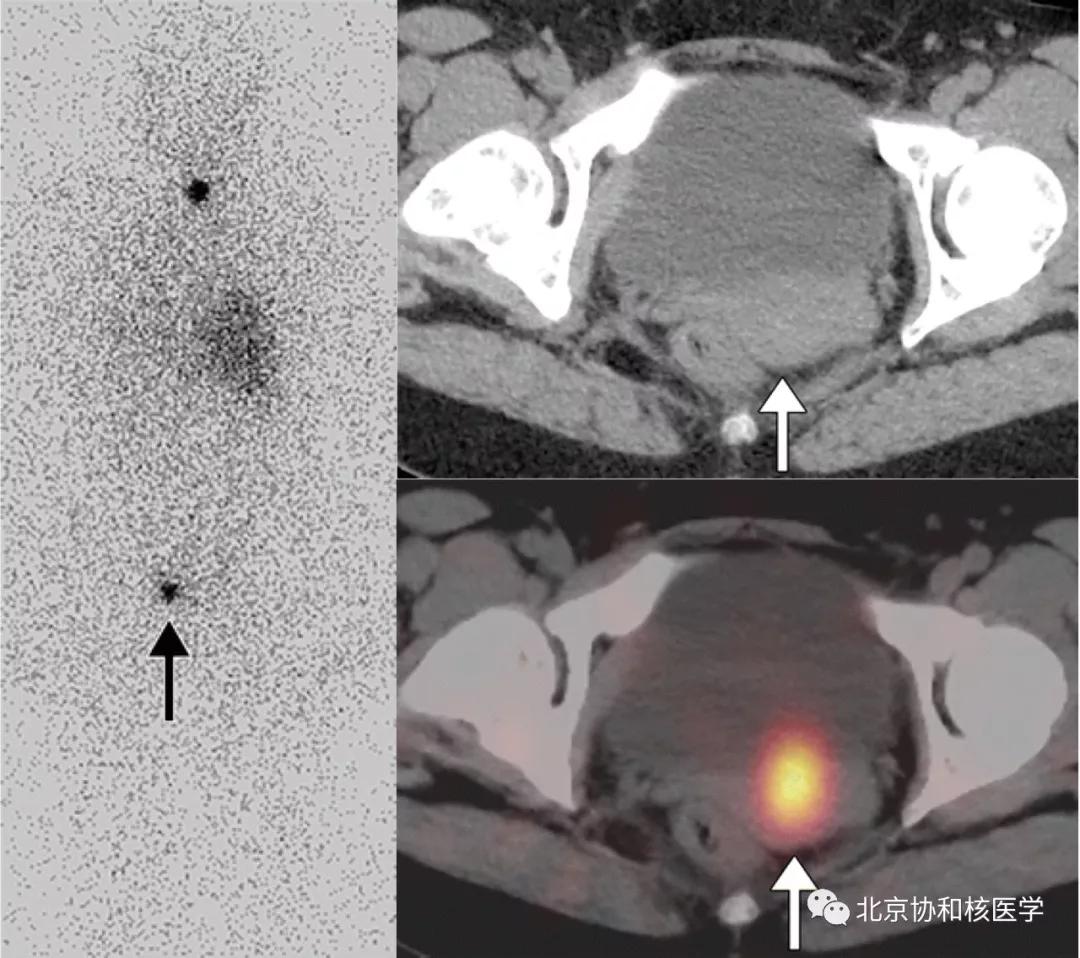

碘在一些囊性病变中也可形成局部滞留,可能由于碘通过被动扩散进入到囊腔中然后滞留,造成假阳性显像。

肝周或肝被膜下囊肿所致碘摄取:

单纯肾囊肿的碘摄取,可能由于囊液与集合系统的交通或碘通过囊肿上皮细胞分泌入囊内滞留形成:

鼻骨骨样骨瘤所致碘摄取,腹部另可见由于巨大肾囊肿所致碘异常摄取: